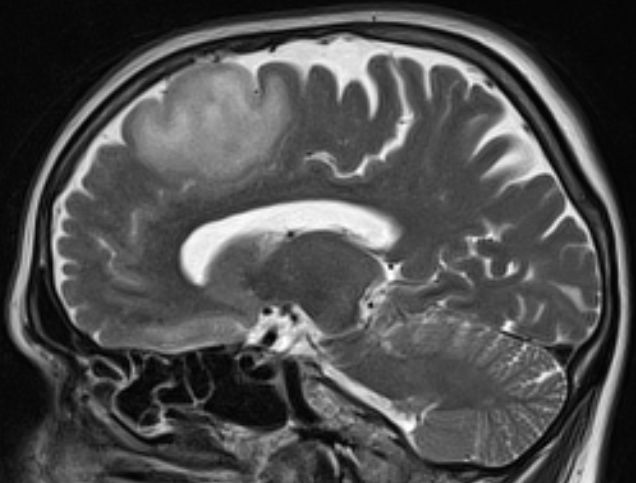

61-jährige Frau mit einem diffusen Astrozytom Grad II | ||

MRT T2 Tse |

MRT T2 Tirm![]() |

MRT T2 Tse![]() |